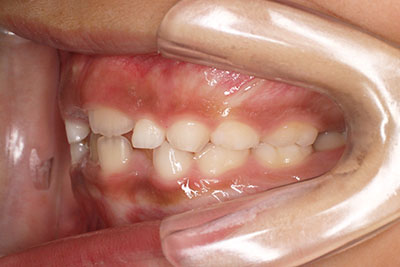

右上の前歯が生えてこない事を気にされ来院されました。 レントゲン写真から、上顎正中に過剰歯が埋伏していることが原因でしたので、抜歯して経過観察。 遅れて、無事に生えてきました。 もし、自然に生えてこない場合は、開窓して、引っぱり出します。(廷出) 状態により、引っぱり出せない場合もあります。 将来的にスペース不足により、上下顎前臼歯部に重度の叢生(がたつき)が予測できますので、がたつきを減らすために、小児矯正で側方拡大を行いました。 小児矯正で側方拡大を行ってもスペースが足りない場合(著しくスペース不足の場合)は、がたつき(叢生、八重歯)が残ります。 残ったがたつき(叢生)は、本格矯正ですべて生え変わった中学生から治せば問題ありません。 来院間隔が平均で1.5カ月でしたので半年ほど治療期間が長いです。